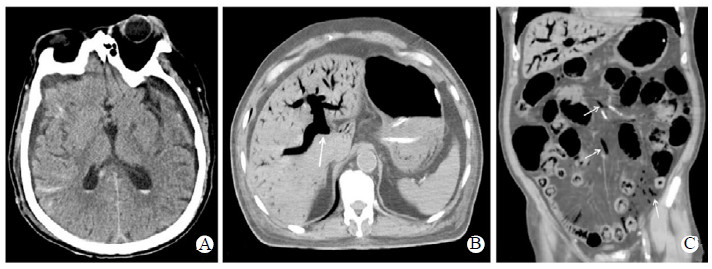

急诊头颅CT:两侧多发脑挫裂伤,多发蛛网膜下腔出血(见图 1A),两侧额颞部少量硬膜下积液,右侧枕顶部皮下软组织肿胀。肋骨CT:左侧1-6肋骨、右侧第4、6、7肋骨多发骨折,右上肺渗出。骨盆X片:右股骨粗隆间骨折。急诊予营养神经、破伤风抗毒素肌注、止痛护胃等治疗,并给予头顶部清创缝合包扎,请神经外科会诊后,表示暂无手术指征。入院后予药物营养神经,控制血压,避免低灌注、高热、低氧血症,抗感染等对症治疗。入院第5天清晨06:12出现心率下降,最低35次/min,指氧饱和度下降,最低至70%,予床边抢救,紧急气管插管维持氧合,胸外按压、肾上腺素静推后心律恢复窦性,70~80次/min,经抢救后患者自主循环恢复。查急诊全腹部CT增强示门静脉气体栓塞(hepatic portal venous gas,HPVG)(见图 1B),肠系膜静脉广泛气体栓塞(见图 1C)。患者11:03再次出现心率下降,39次/min,大动脉搏动消失,立即予床边胸外按压,肾上腺素1 mg静推后,于11:09颈动脉搏动恢复,进行床边心电图检查:心房颤动伴快心室率,完全性右束支传导阻滞,左前分支传导阻滞,ST段改变;患者12:12再次心率直线下降至48次/min,患者血压测不出,氧饱和度测不出,大动脉搏动消失,予胸外按压,予肾上腺素静推,立即予床边胸外按压,每3分钟肾上腺素静推,12:23颈动脉搏动恢复,予去甲肾上腺素维持血压,患者呼吸心跳骤停心肺复苏术后循环极度不稳定,遂于20:50予ECMO上机治疗。患者于入院第6天死亡。

| A: CT示多发脑挫裂伤、多发蛛网膜下腔出血、两侧脑室后角积血;B: 门静脉主干及分支多发积气(箭头所指处);C: 肠系膜静脉广泛多发积气(箭头所指处) 图 1 患者急诊头颅CT与腹部CT影像 |